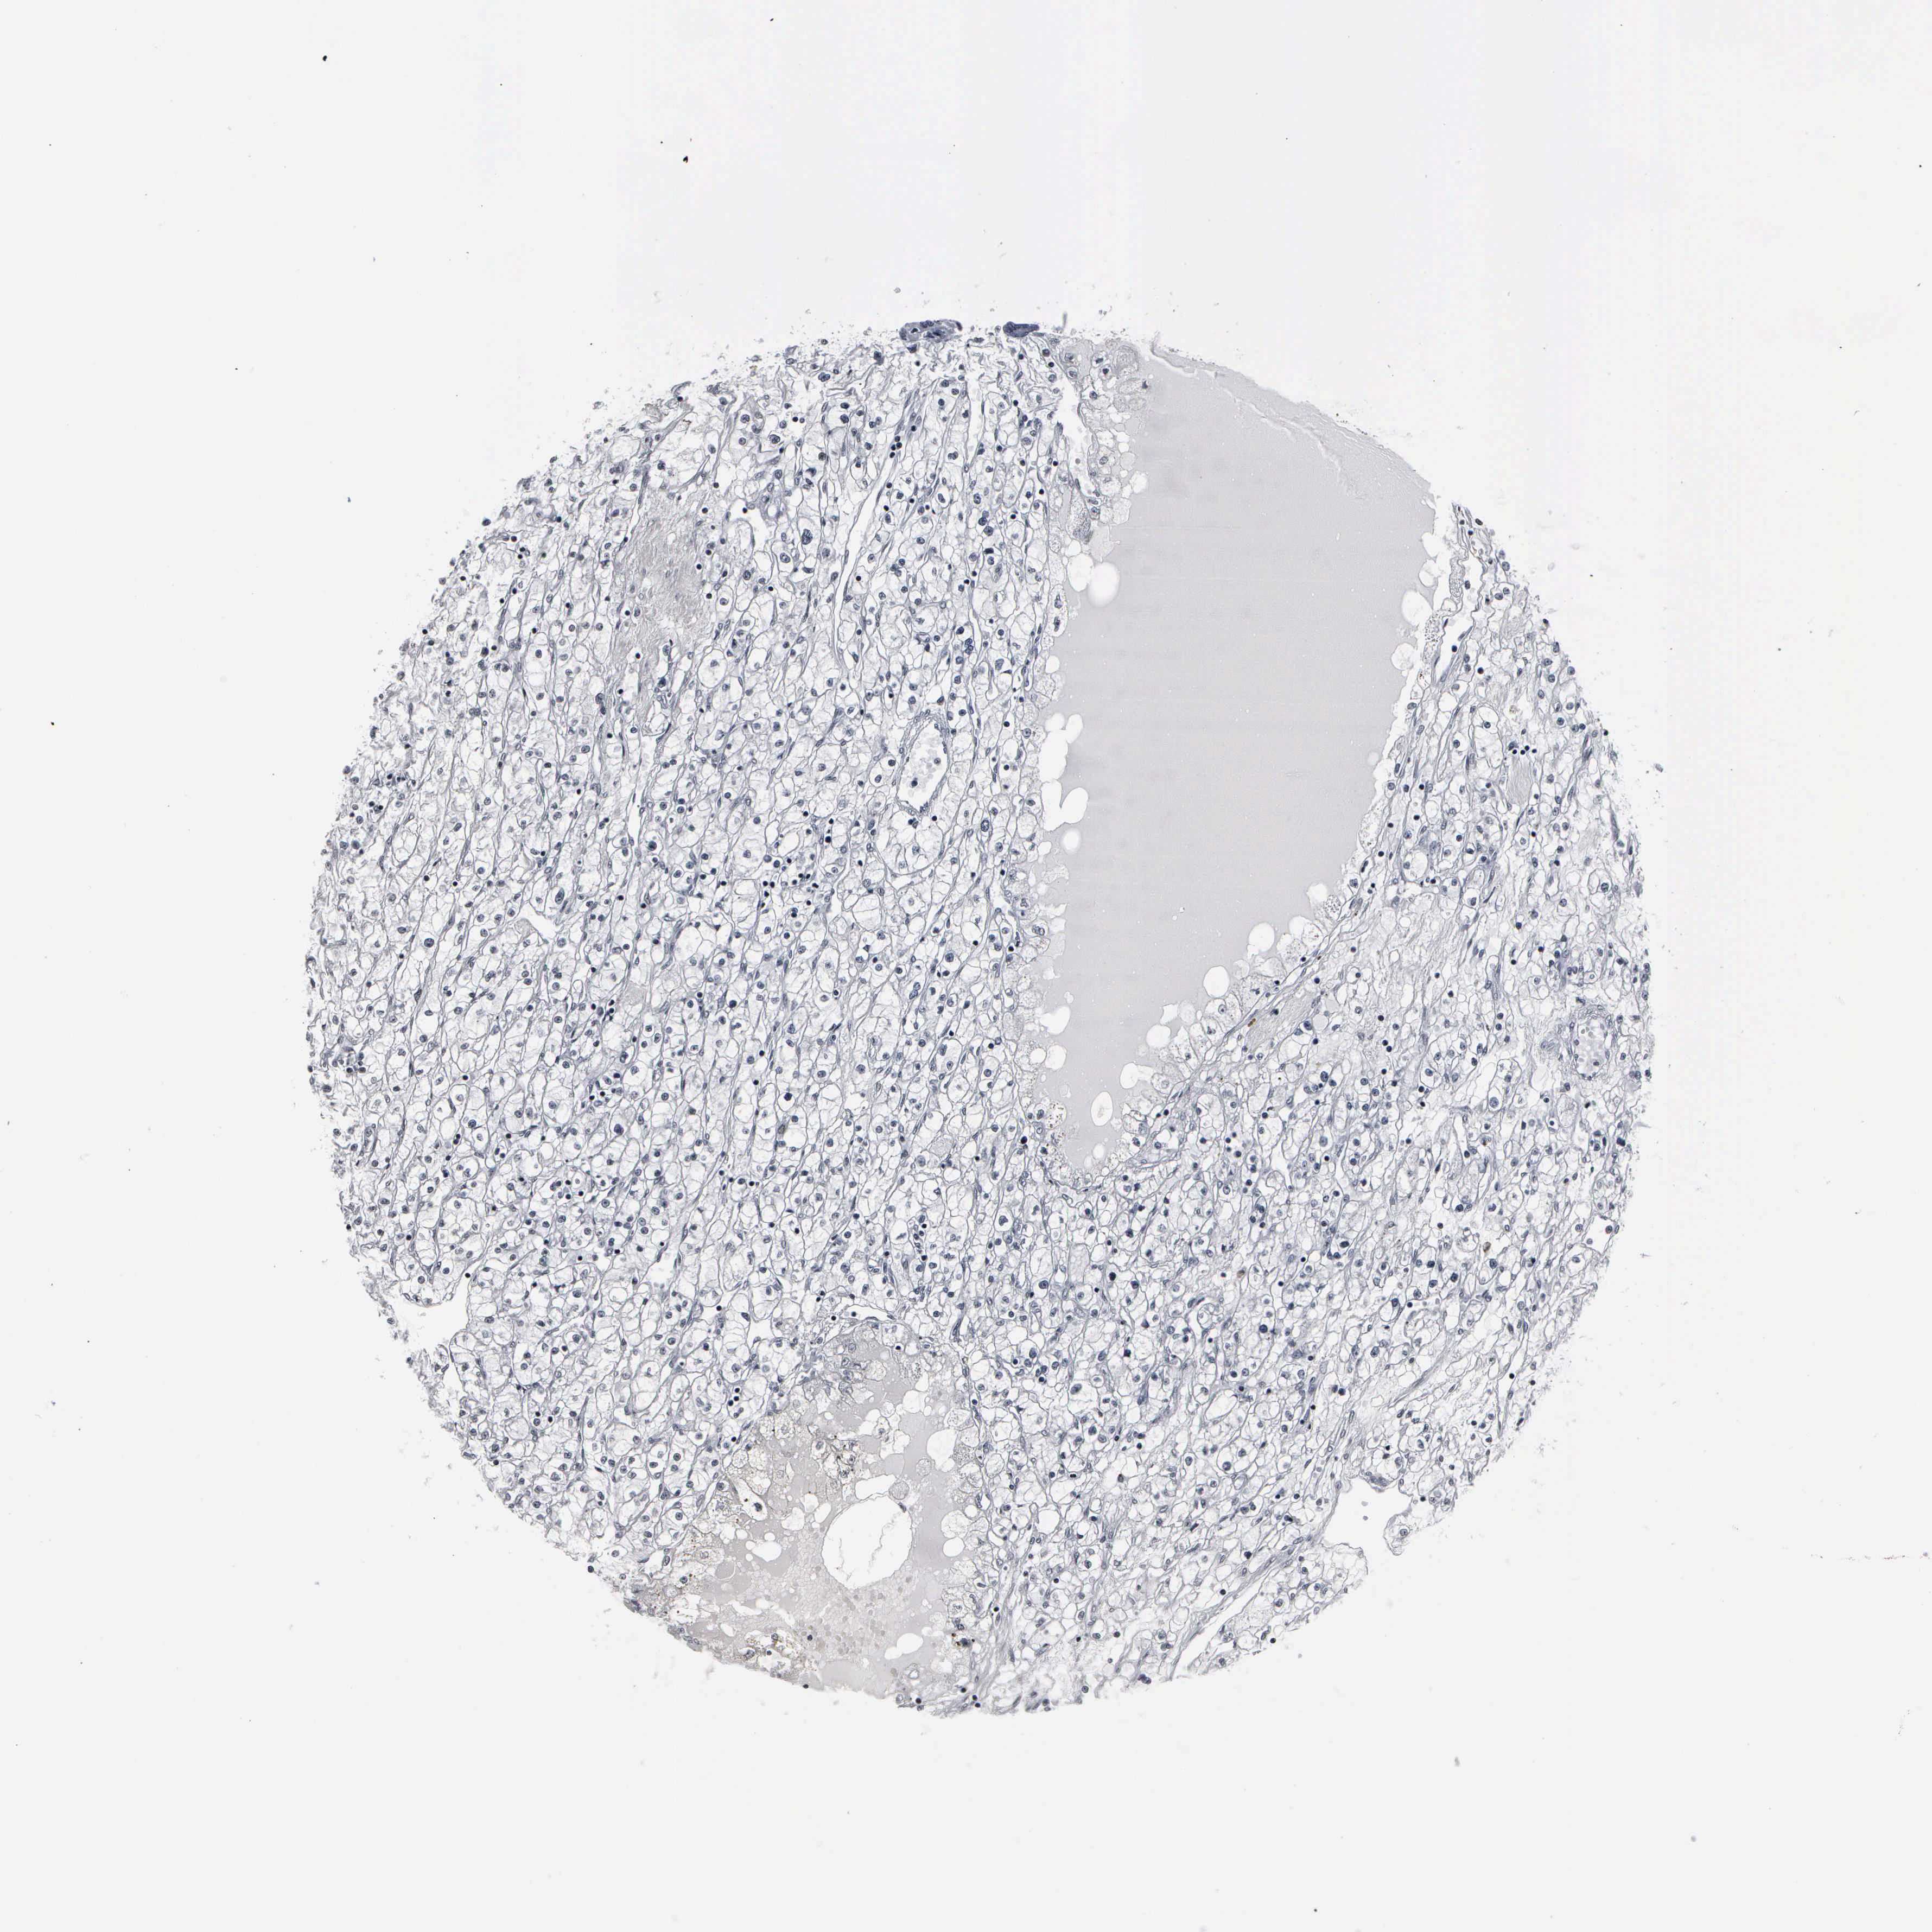

CANCER RENAL CANCER Show tissue menu

KICH TCGA KIRC TCGA KIRC VALIDATION KIRP TCGA PROTEIN RCC CPTAC PROTEIN EXPRESSION